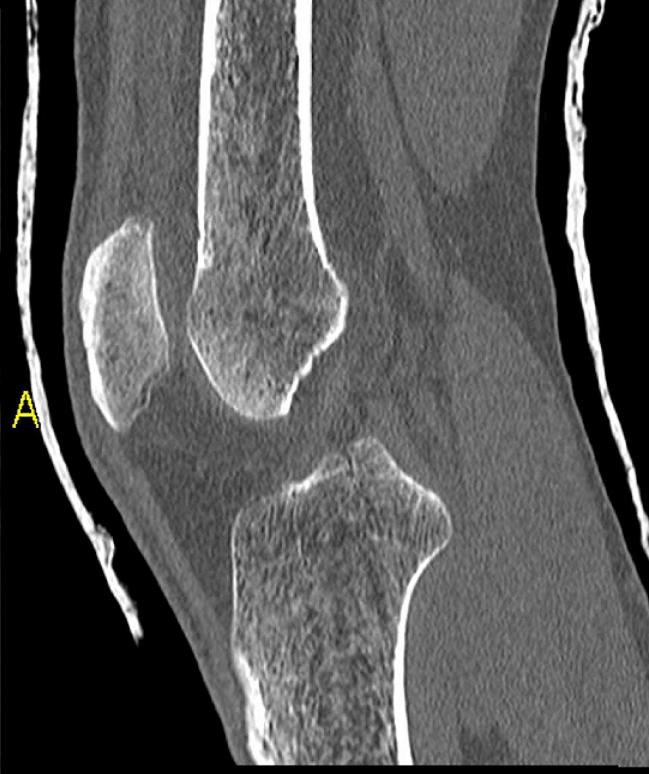

Die Dental-CT bietet im Vergleich zum konventionellen Orthopantomogramm (OPG) die Option der artefakt- und überlagerungsfreien Dentalrekonstruktion in jeglicher Ebene. Die Strahlenbelastung ist sicher höher als bei OPG und DVT, die diagnostische Wertigkeit ist jedoch auch höher. Das Röntgenverfahren reicht bei mangelnder Dreidimensionalität nicht für alle präoperative Fragestellungen, das DVT ist nur für knöcherne Hochkontrastbildgebung geeignet.

Indikationen zur Dental-CT sind dagegen alle Fragen im Bereich von Mund und Mittelgesicht wie Raumforderungen, Entzündungen, retinierte Zähne, angeborene Dysplasien, Diagnostik vor kieferchirurgischen Eingriffen, Zahnextraktionen oder Implantaten und Kontrollen nach therapeutischen Eingriffen. Für Kinder und Jugendliche besteht die Möglichkeit der Dosisreduktion.